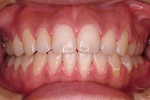

CASE5

小学1年の頃から前歯の噛み合せが逆でした。

同級生が通っていたので来ました。

(11歳/男性)↓

概要・担当医コメント:反対咬合・前歯部咀嚼障害↑

/マルチブラケット装置/非抜歯/動的治療期間24ヶ月(25回)/費用概算:60万円

治療前は虫歯のコントロールが難しい状態でしたが,矯正治療を開始してからは歯磨きを丁寧にしてくれるようになり,甘味摂取習慣の改善も行って頂いた効果があり,その後の虫歯の発生は無く現在に至っています.